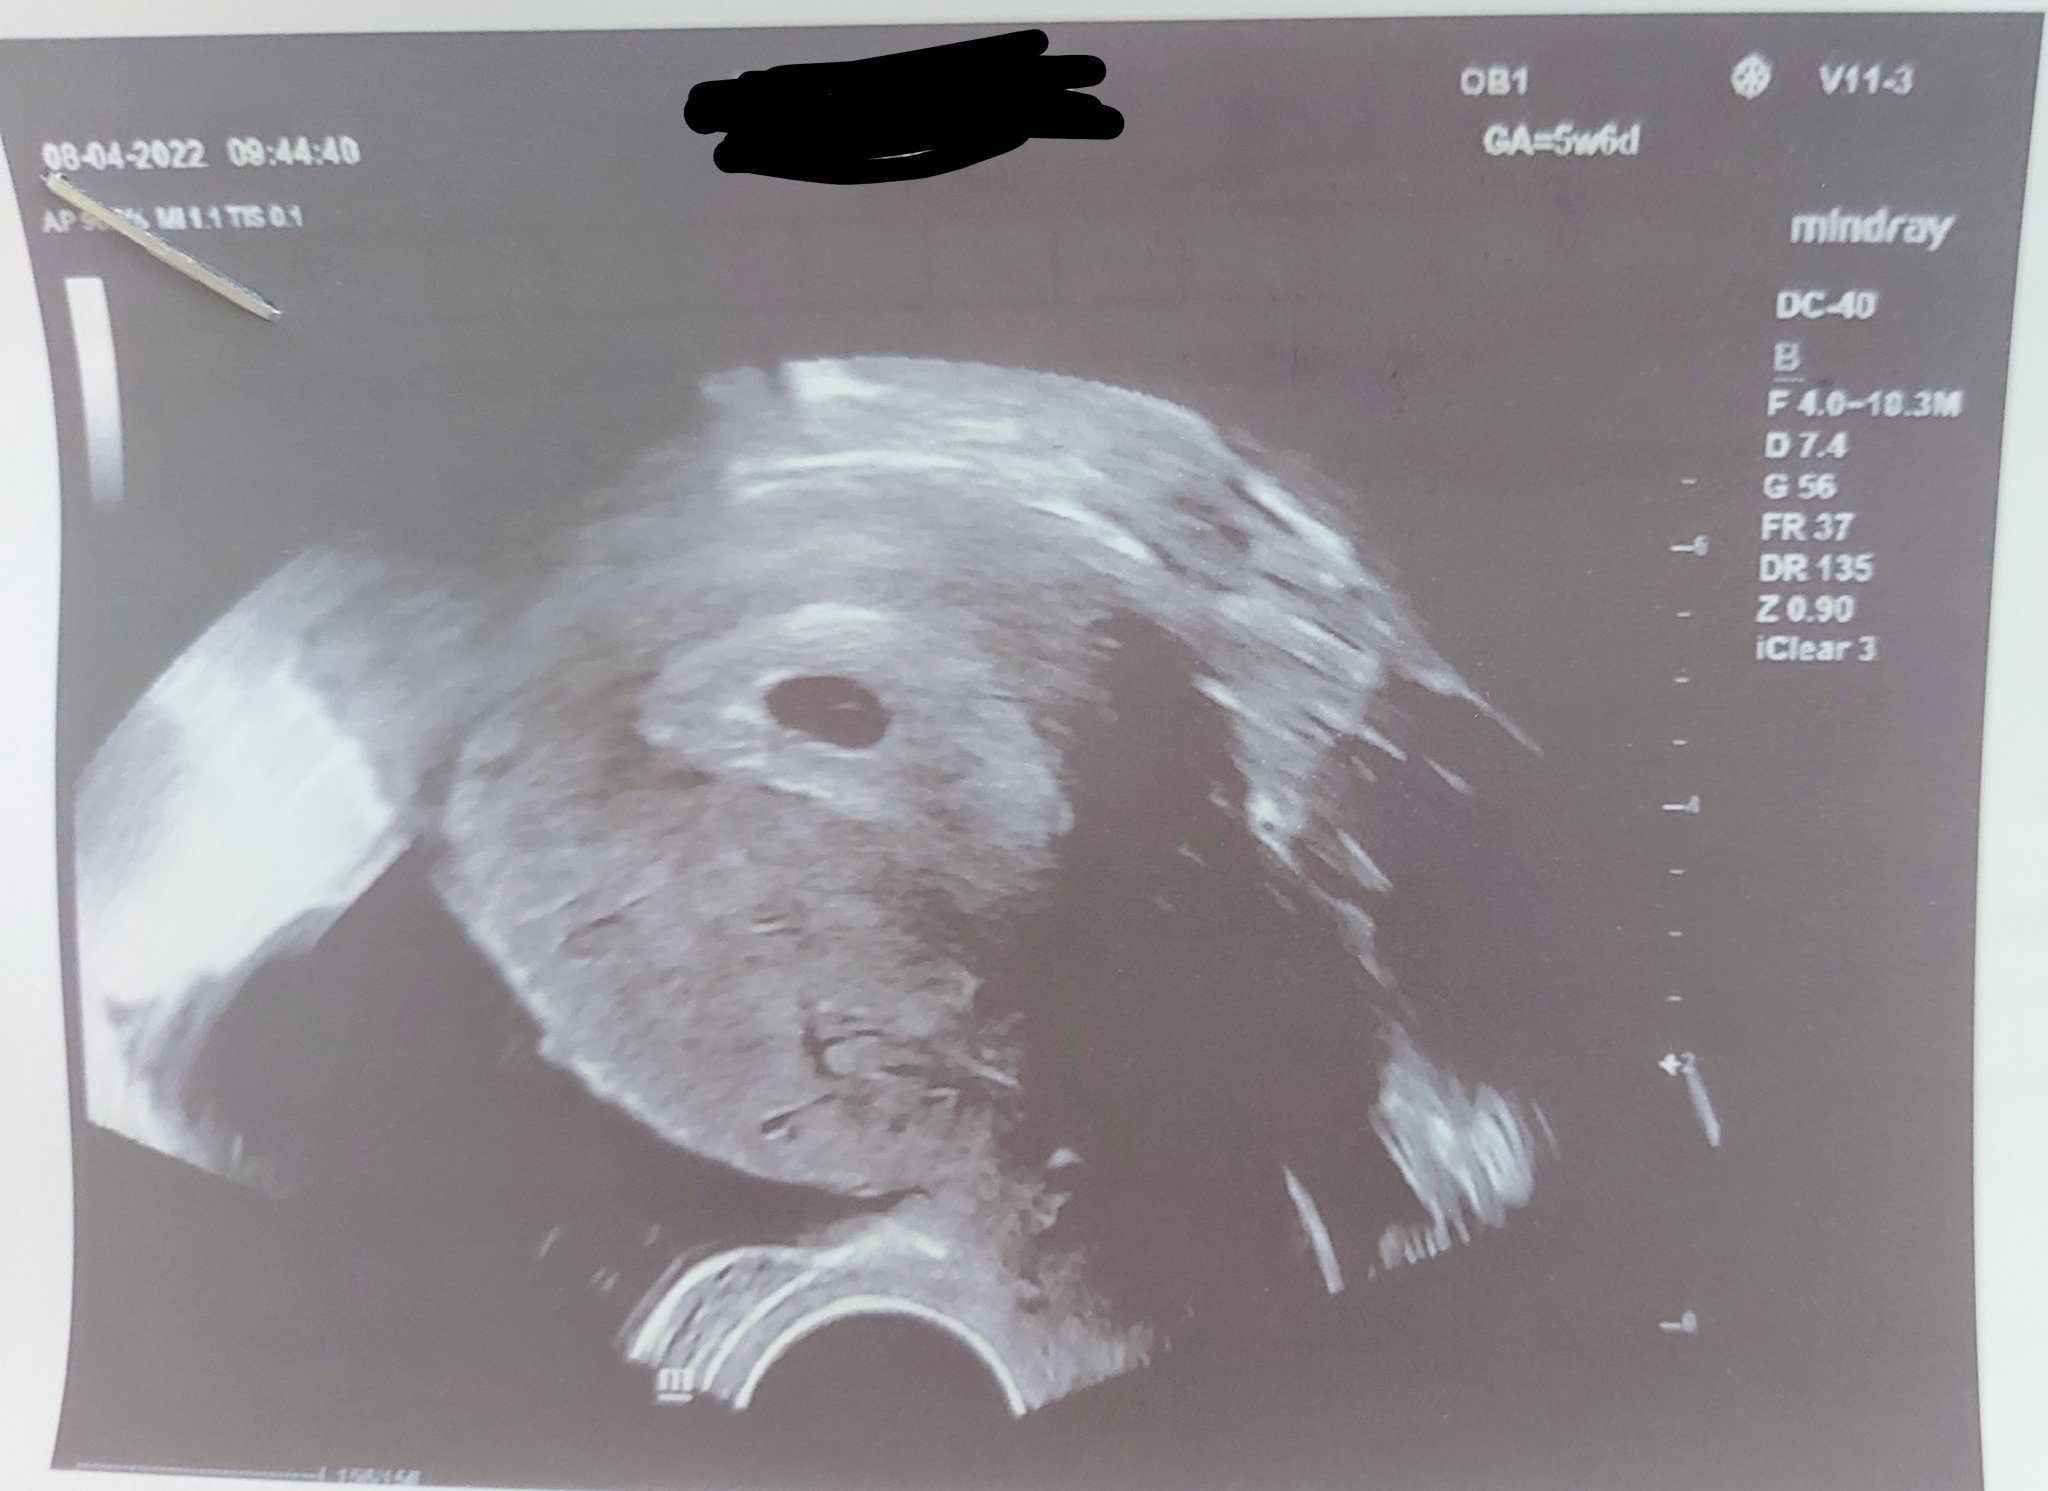

Кога за първи път усещат сърцето на бебето?